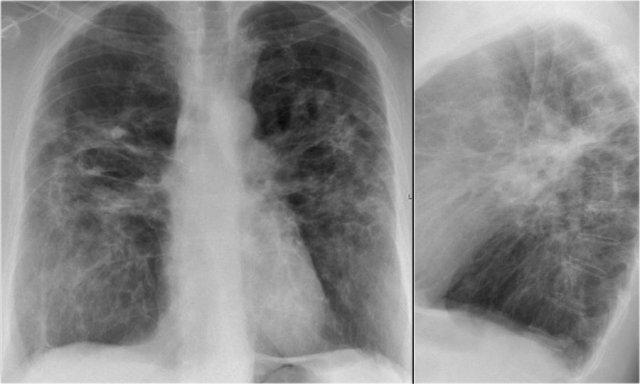

Đây là một bệnh nhân khác mắc sarcoidosis.

Có mất thể tích ở thùy trên do xơ hóa.

Hình ảnh bên trái cũng cho thấy các đám mờ trong phổi.

Trên HRCT thấy các nốt mịn.

Phim X-quang ngực thẳng theo dõi cho thấy hầu hết các bất thường phổi đã được hấp thu.

Xơ hóa vẫn còn tồn tại.